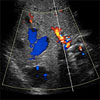

Ultrasound depicting a

Liver Arteriovenous Malformation (AVM).

A liver ultrasound uses reflected sound waves to produce a picture of the organs in the abdomen. No radiation is used during this study, and it is therefore the preferred method for screening liver AVMs.